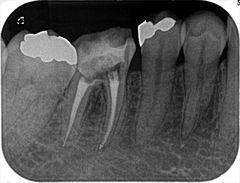

髄床底に穿孔していた右下第一大臼歯の再根管治療を行いました。2018.08.10

左下奥歯のメタルコアとヤスリのカケラを取り除き再根管充填を行いました。